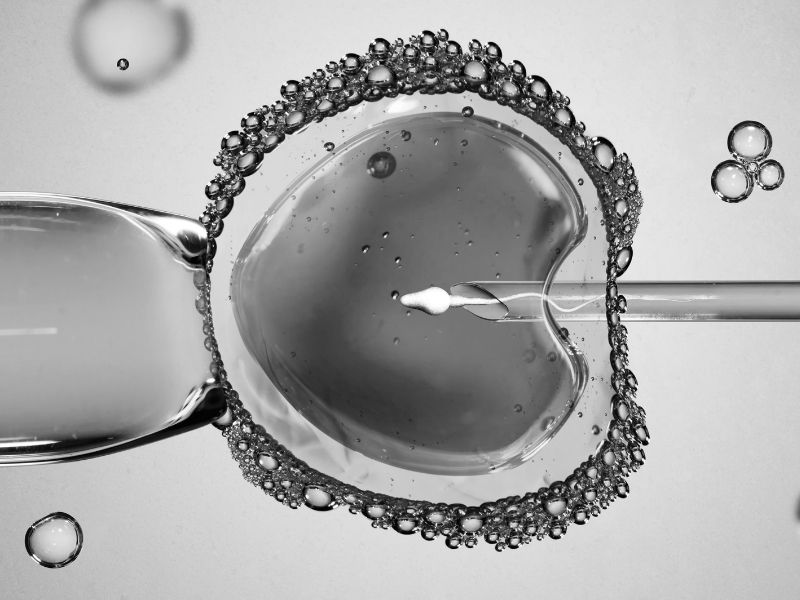

• TÜP BEBEK TEDAVİSİ: Amaç fazla sayıda yumurta üretmektir. Kadına bu amaçla hormon içeren ilaçlar verilir. Büyüyen yumurtalar cerrahi işlem ile kadından toplanır. Toplanan yumurtalar, erkekten alınan spermler ile labarotuvar ortamında birleştirilir. Oluşan embriyolardan bir veya ikisi kadına transfer edilir.

Tüp Bebek Nedir?

Yardımcı üreme yöntemidir. Kadından alınan yumurtanın, erkek üreme hücresi sperm ile dış ortamda birleştirilerek gerçekleştir…